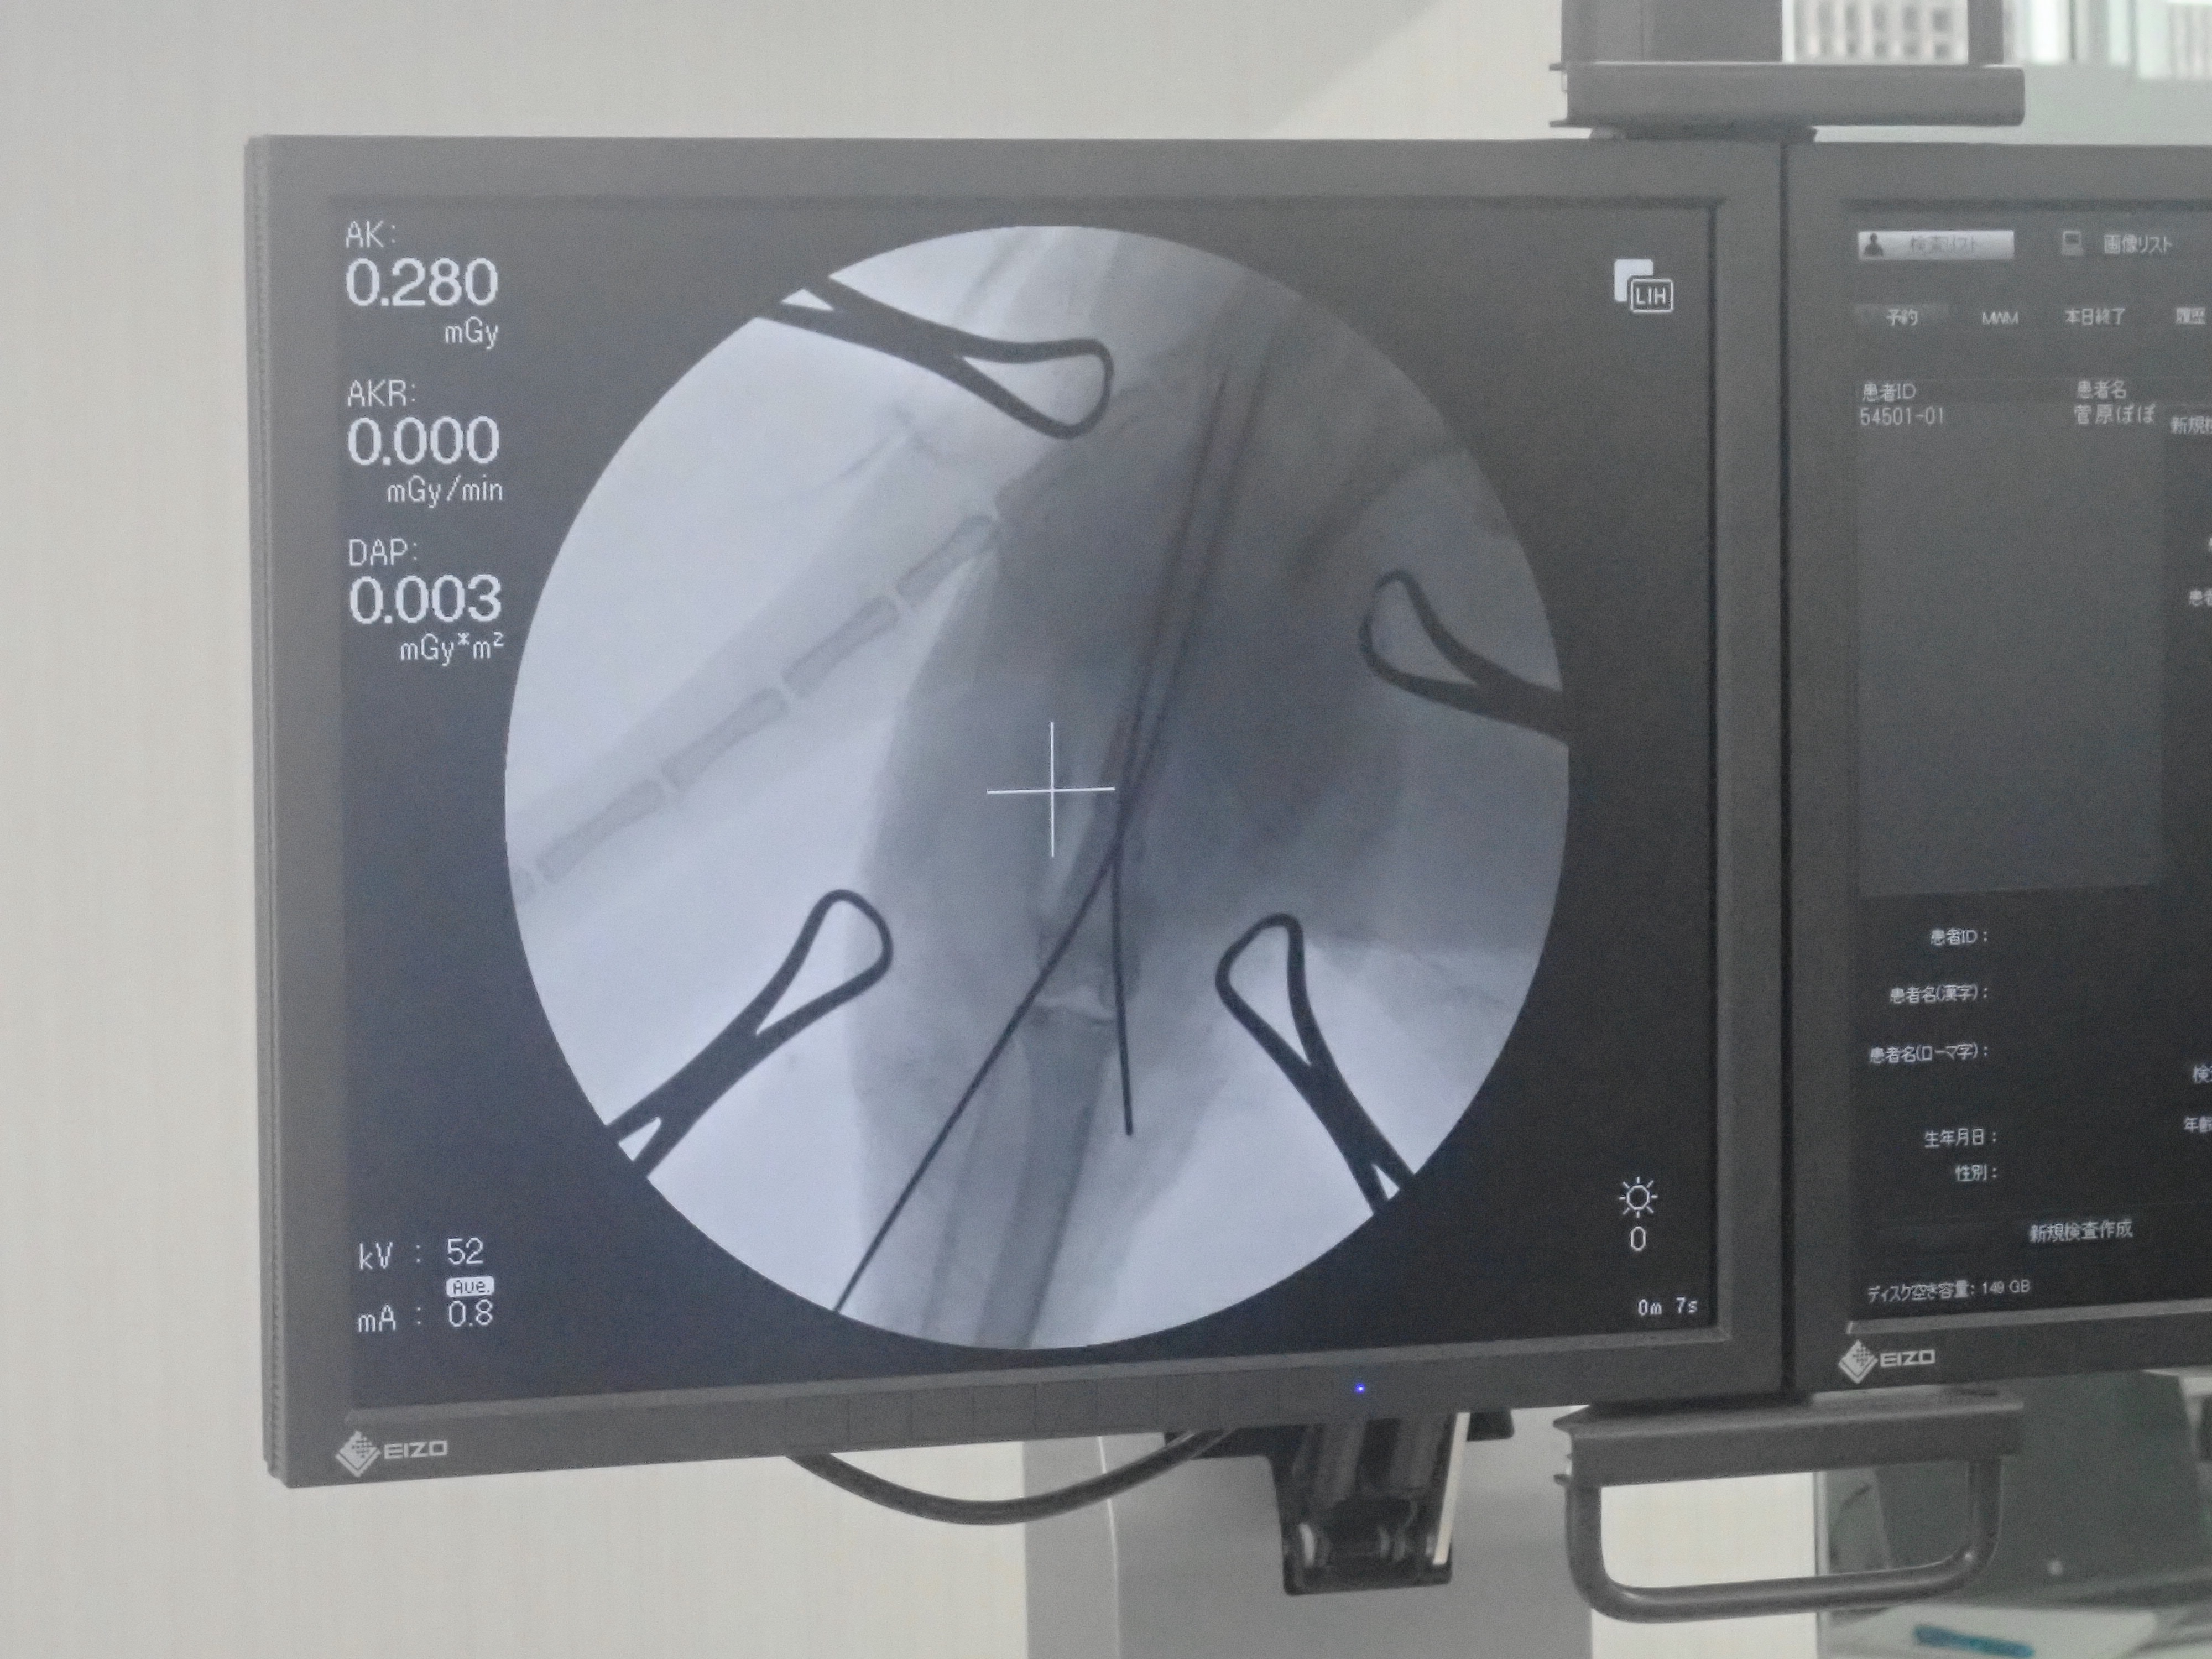

最初に髄内ピンを挿入してCアームという機械で確認しているところです。